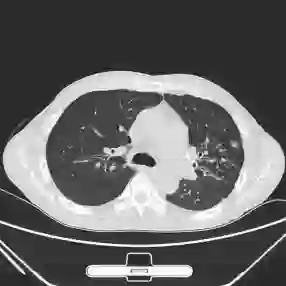

This paper proposes applying a novel deep-learning model, TBDLNet, to recognize CT images to classify multidrug-resistant and drug-sensitive tuberculosis automatically. The pre-trained ResNet50 is selected to extract features. Three randomized neural networks are used to alleviate the overfitting problem. The ensemble of three RNNs is applied to boost the robustness via majority voting. The proposed model is evaluated by five-fold cross-validation. Five indexes are selected in this paper, which are accuracy, sensitivity, precision, F1-score, and specificity. The TBDLNet achieves 0.9822 accuracy, 0.9815 specificity, 0.9823 precision, 0.9829 sensitivity, and 0.9826 F1-score, respectively. The TBDLNet is suitable for classifying multidrug-resistant tuberculosis and drug-sensitive tuberculosis. It can detect multidrug-resistant pulmonary tuberculosis as early as possible, which helps to adjust the treatment plan in time and improve the treatment effect.